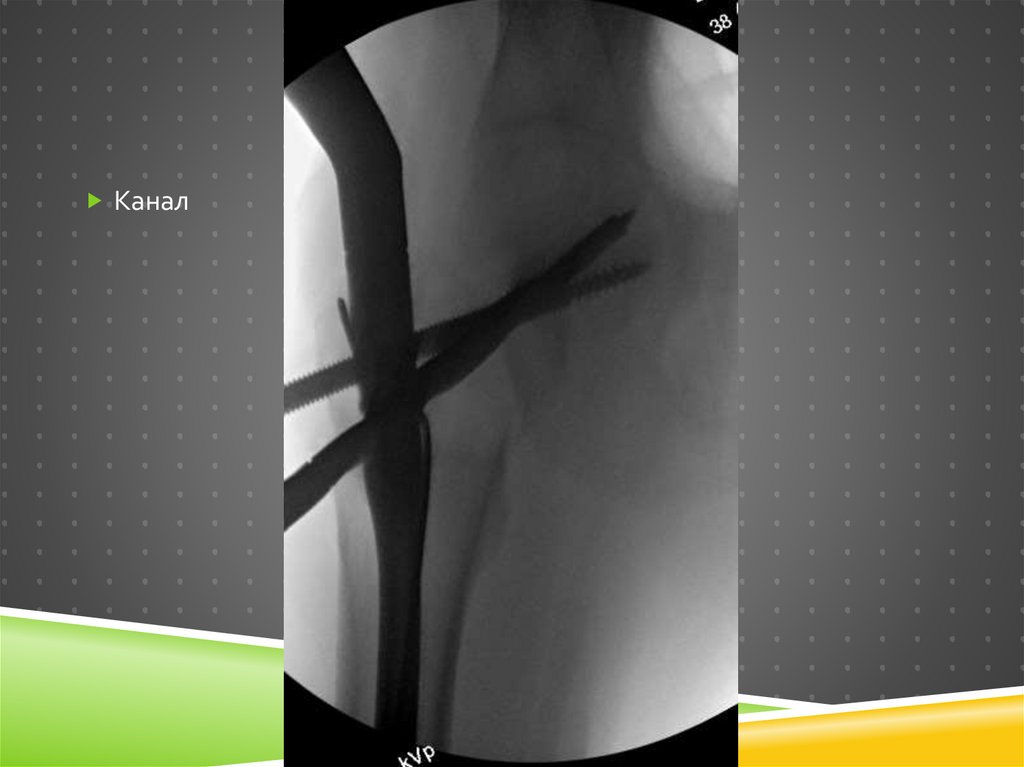

Канал

83.

Винт

84.